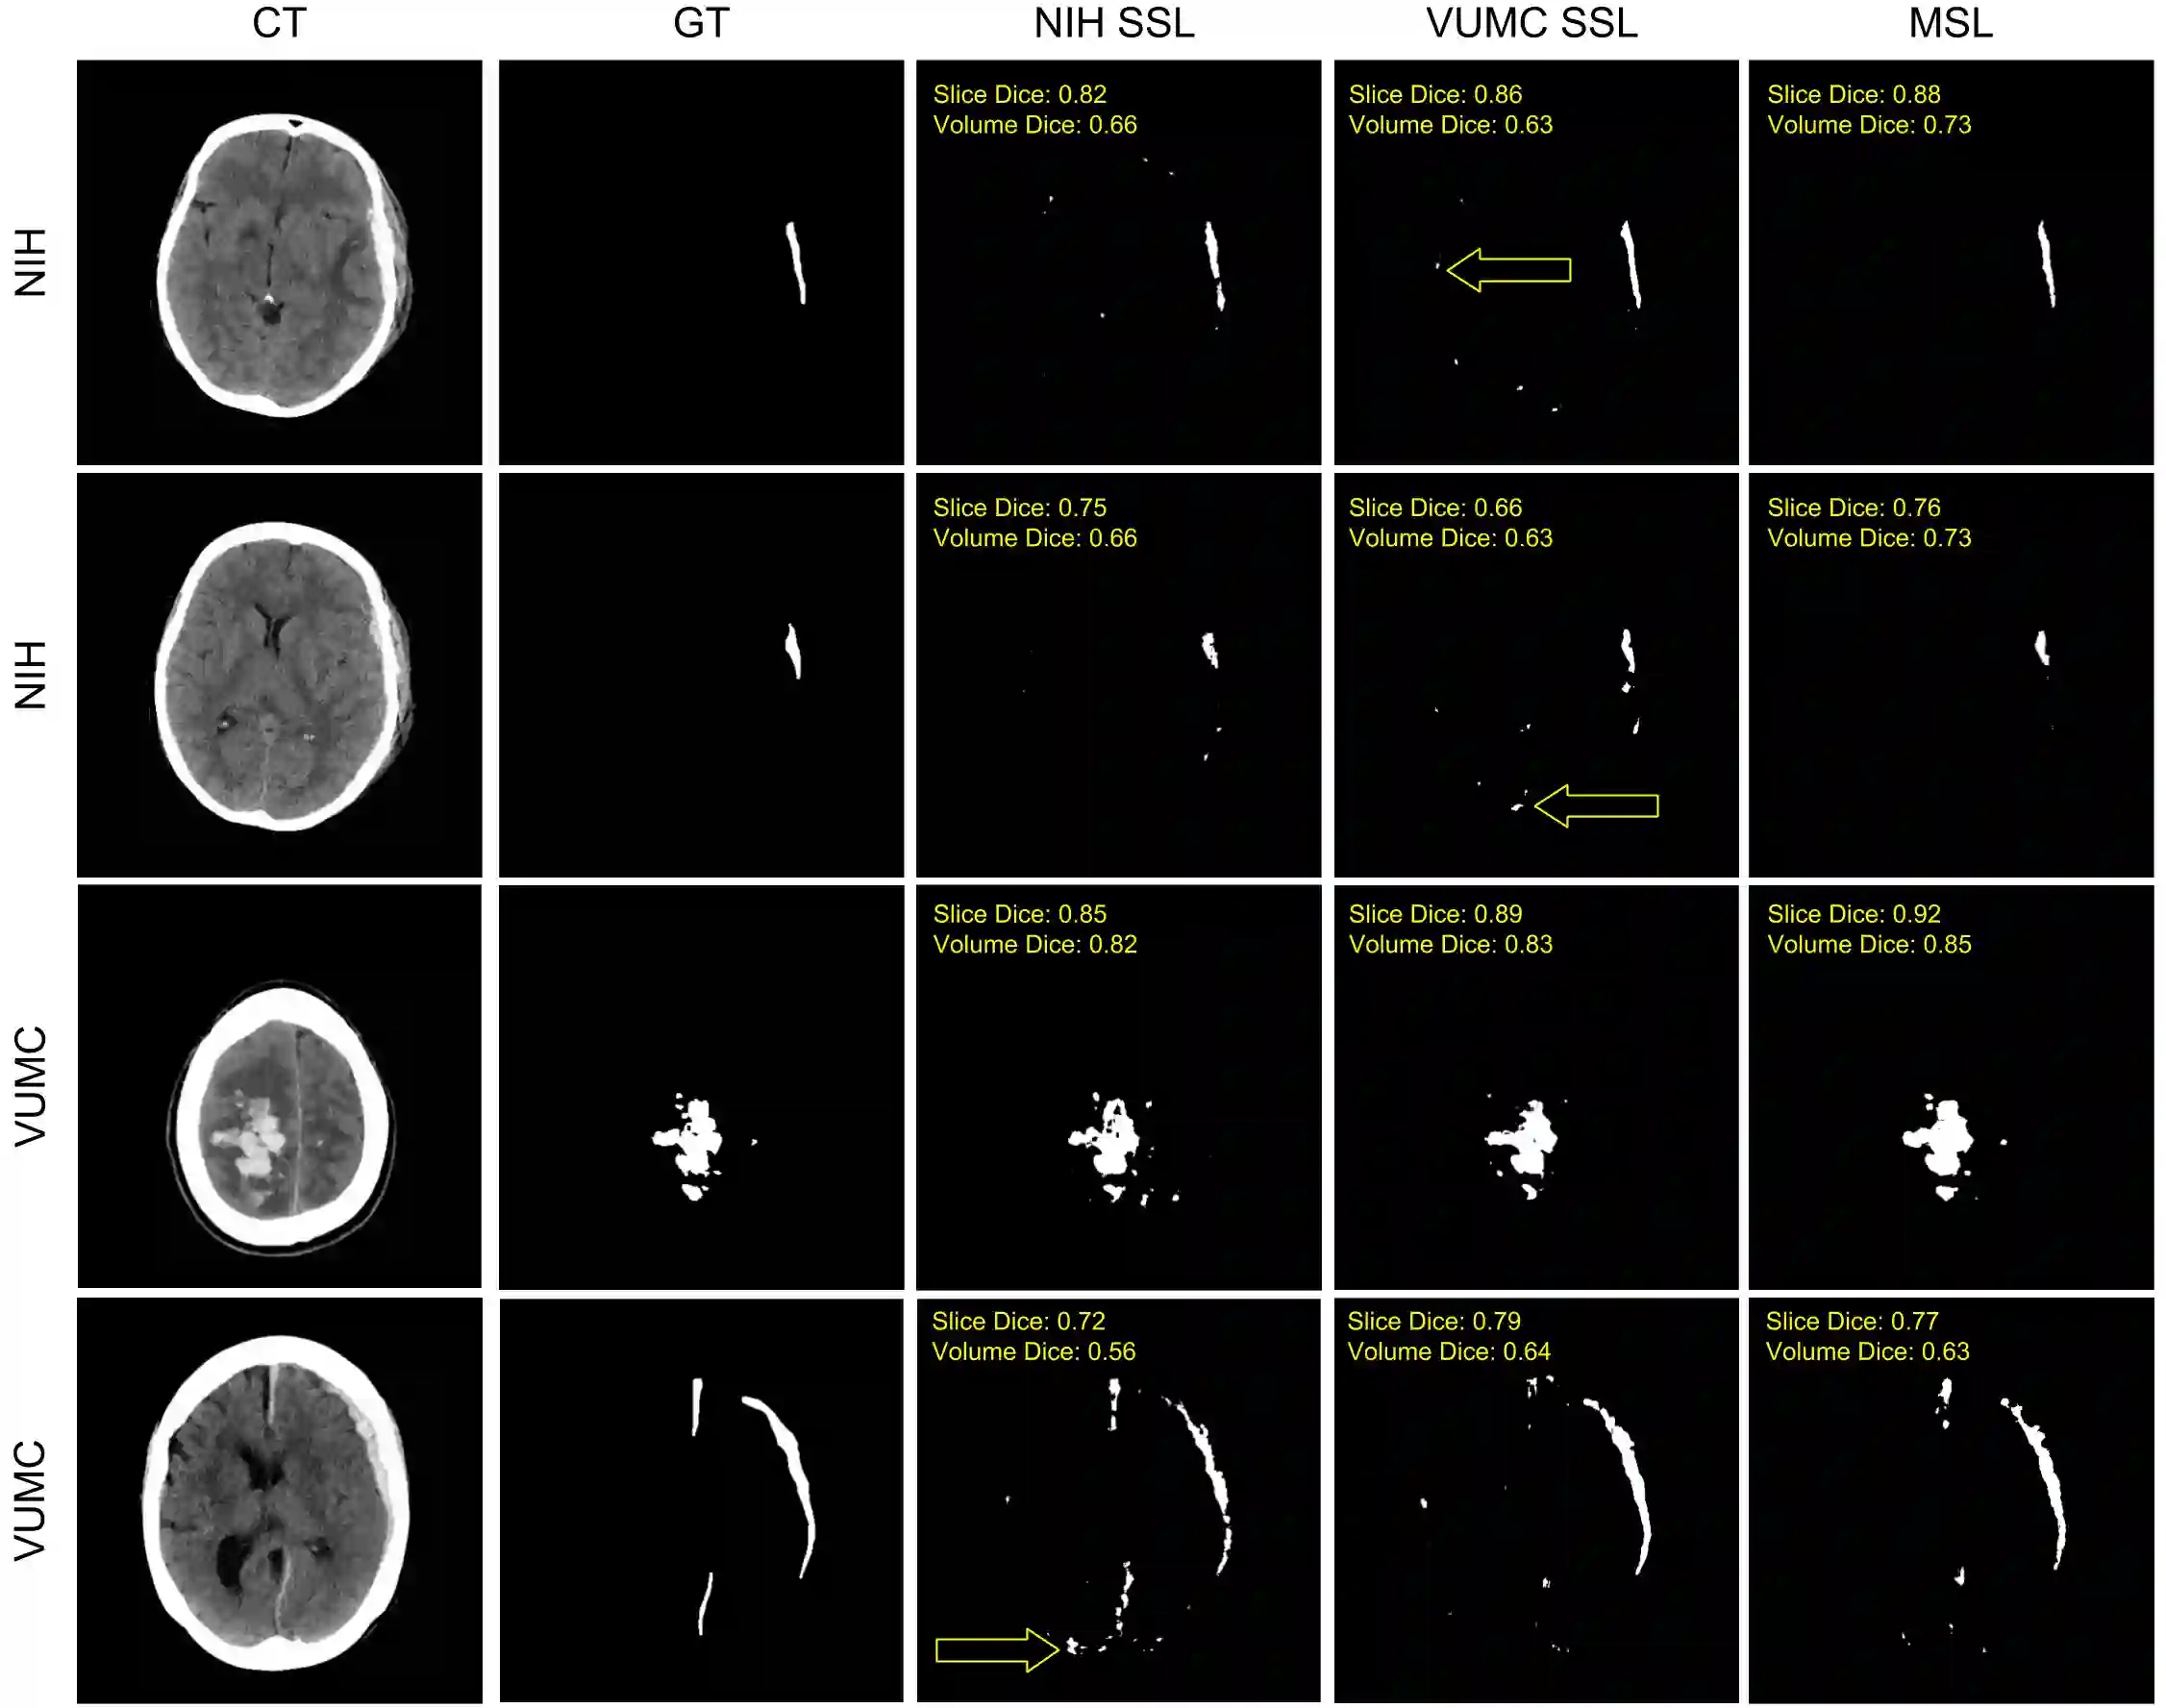

Machine learning models are becoming commonplace in the domain of medical imaging, and with these methods comes an ever-increasing need for more data. However, to preserve patient anonymity it is frequently impractical or prohibited to transfer protected health information (PHI) between institutions. Additionally, due to the nature of some studies, there may not be a large public dataset available on which to train models. To address this conundrum, we analyze the efficacy of transferring the model itself in lieu of data between different sites. By doing so we accomplish two goals: 1) the model gains access to training on a larger dataset that it could not normally obtain and 2) the model better generalizes, having trained on data from separate locations. In this paper, we implement multi-site learning with disparate datasets from the National Institutes of Health (NIH) and Vanderbilt University Medical Center (VUMC) without compromising PHI. Three neural networks are trained to convergence on a computed tomography (CT) brain hematoma segmentation task: one only with NIH data,one only with VUMC data, and one multi-site model alternating between NIH and VUMC data. Resultant lesion masks with the multi-site model attain an average Dice similarity coefficient of 0.64 and the automatically segmented hematoma volumes correlate to those done manually with a Pearson correlation coefficient of 0.87,corresponding to an 8% and 5% improvement, respectively, over the single-site model counterparts.